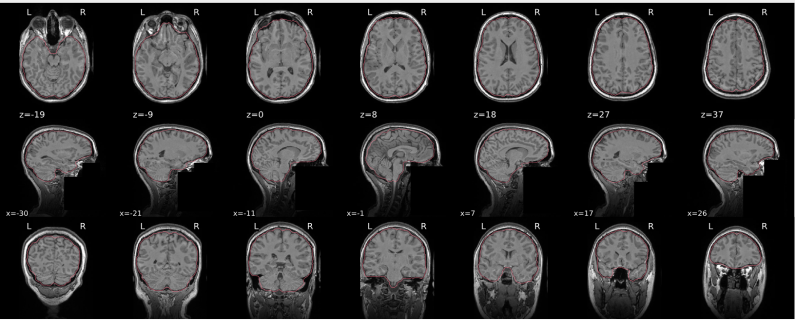

T1w skull stripping

Skull stripping is the process separating the brain (cortex and cerebellum) from the skull. The red line follows the outline of the brain and it separates it from the skull.

Example of a good subject

- There are no skull stripping errors, such as portions of the brain missing, or too much of the skull retained

- The red line follows the outline of the brain

Example of a bad subject

- There are skull stripping errors, such as portions of the brain missing, or too much of the skull retained

- NOTE: check all the images (slices) in the report. If only one image (slice) looks problematic, it is possible that the subject is okay and it is just a visual issue in that particular screenshot

Summary

| Good | Bad |

|---|---|

| The brain is fully inside the red line | Structures like the cranium or the eyes are inside the red line |

| No important brain structures are outside of the red line red line follows the natural outline of the brain | Important brain structures are missing inside of the red line |

-> if only one slice is problematic, it could be an issue related to the visual depiction of the data instead of an issue related to the test subject